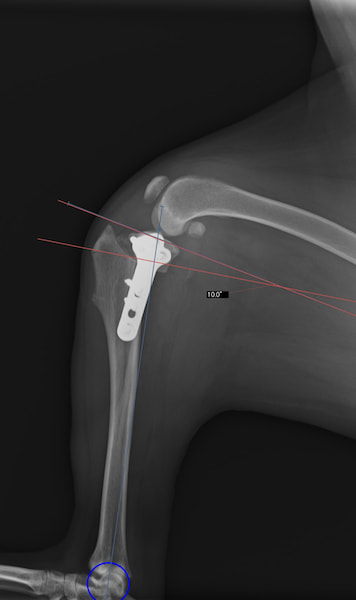

本症例は、走った後に左後肢を挙上していることを主訴に来院されました。触診時に左膝関節のクリック音を聴取、レントゲン検査にて左脛骨の前方変位が認められました。術中に、前十字靱帯の断裂及び内側半月板の損傷、内側の軟部組織の顕著な腫脹を確認。半月板切除、TPLOを実施しました。周囲組織への炎症の波及もあったため回復に時間を要しておりますが、徐々に跛行頻度は減少傾向にあり、現在も経過観察中です。術前に約29°あったTPAは術後に約10°まで矯正されました。

術前写真

術後写真

手術前後のTPA(脛骨高平部の角度)を測定しています。

約29°から約10°へ矯正されています。